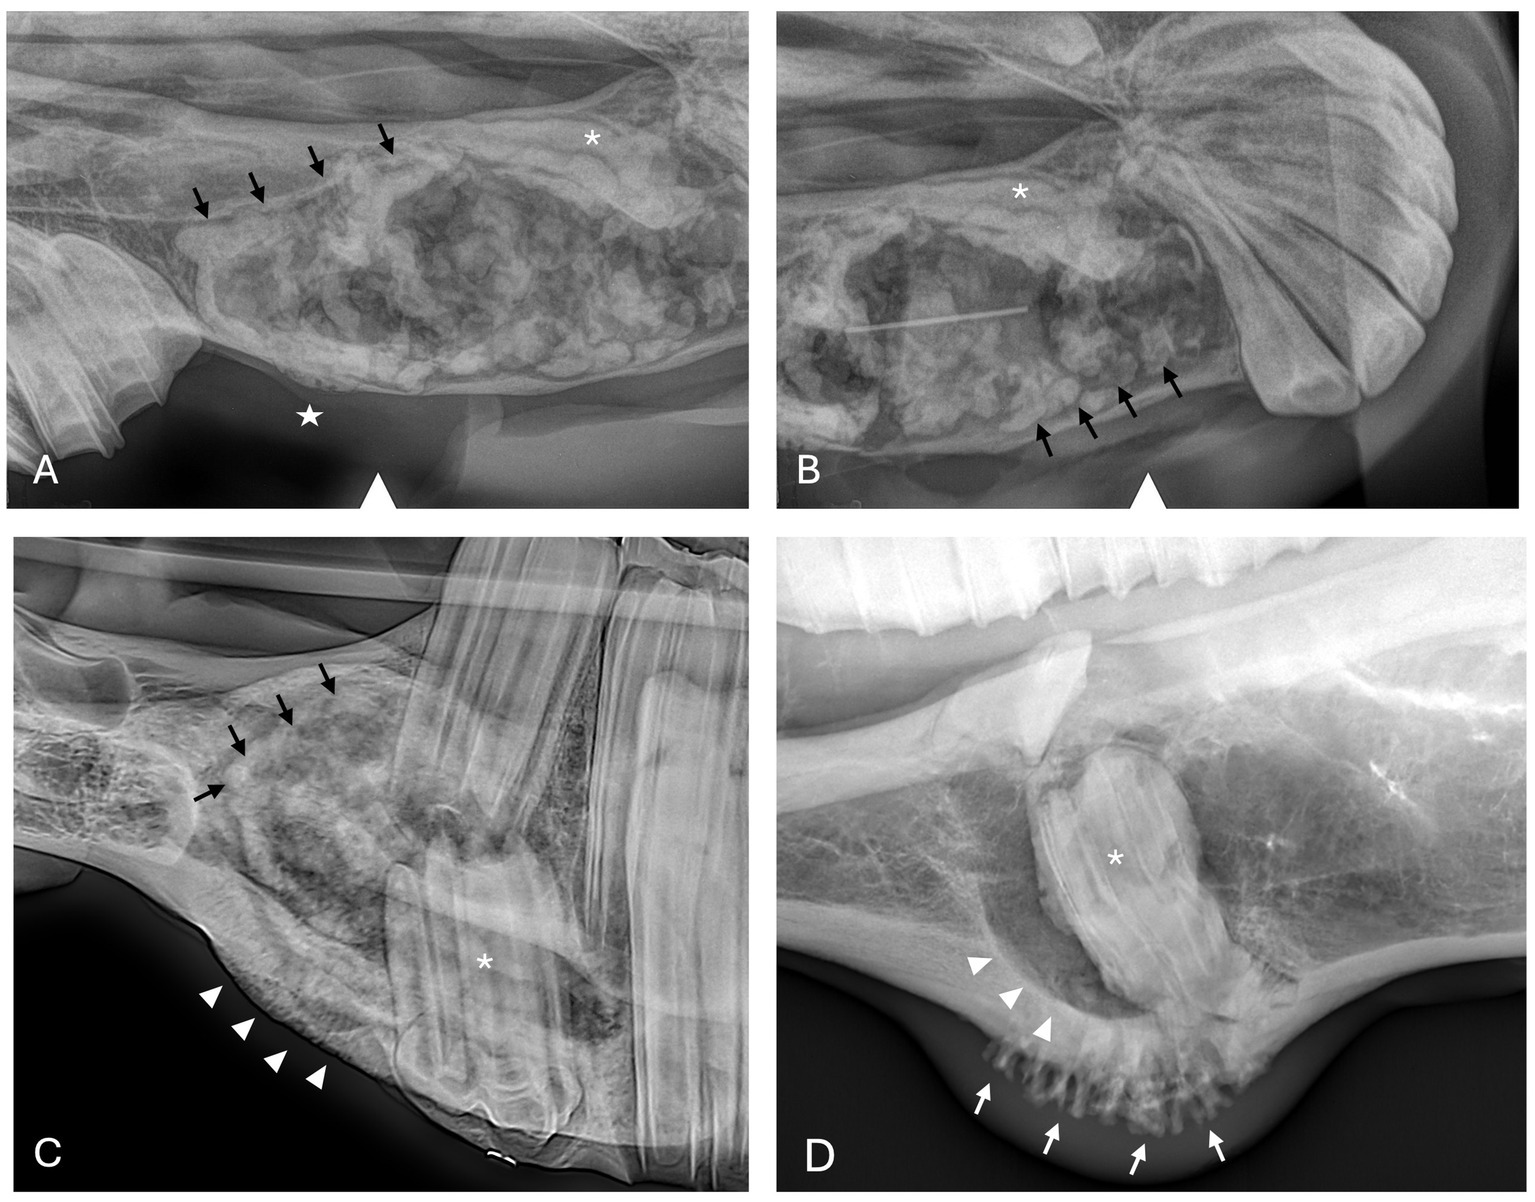

Oral examination findings in the region of the lesion are listed in Table 1. The clinical signs of all cases are listed in Tables 2, 3 according to mass type and location. The most common clinical sign was facial swelling which accounted for 13/17 (76.5%) cases (Figure 1). Missing or unerupted teeth was the second most common clinical sign affecting 7/17 (41.2%) cases. Nasal discharge and respiratory issues (stertor, increased respiratory rate or effort) were the third most common clinical signs and affected 4/17 (23.5%) cases. Other clinical signs included halitosis (3), cystic cavity packed with debris (2), and orofacial draining tracts (1). All dentigerous cysts had facial swelling and unerupted teeth (6/6). Bone cysts were accompanied by facial swelling (4/6, 66.7%) and respiratory issues (2/6, 33.3%). Complicated crown fractures were present in 3/17 (17.6%) cases and were diagnosed in a single case of UIL, BC and RC. A periapical abscess was diagnosed in a single case of a RC. Dysplastic teeth were diagnosed in 4/17 (23.5%) cases. There was no evidence of endodontic or periodontal pathology in 4/17 (23.5%) cases diagnosed in 3 BC and 1 UIL.

Figure 1. Facial swelling. (A) Case 11 right caudal mandibular facial swelling (white arrows) secondary to bone cyst (image courtesy of Easley equine dentistry). (B) Case 5 right rostral maxillary facial swelling (white arrows) secondary to radicular cyst. (C) Case 8 left mandibular facial swelling (white arrows) secondary to bone cyst. (D) Case 16 left mandibular facial swelling (white arrows) secondary to dentigerous cyst.

Radiographic findings are reported based on lesion type (Table 4) and location (Table 5). The most prevalent radiographic finding was tooth involvement in 16/17 (94.1%) cases followed by multiloculated lesions and increased soft tissue opacity in 14/17 (82.4%) cases, respectively (Figures 2–4). Rarefication of the surrounding bone (cortical thinning) was the third most common imaging finding identified in 13/17 (76.5%) of cases. All lesions had tooth involvement except for 1 bone cyst lesion. Radiographically unerupted teeth were 100% associated with dentigerous cysts (6/6) of which 83% (5/6) of the unerupted teeth were dysplastic (Figure 2). Thirty-three percent (2/6) of dentigerous cysts were associated with additional irregular dental material, and both of these lesions were located within the rostral maxilla (Figure 2). Dysplastic teeth also occurred in 2/6 (33%) of bone cysts (Figure 3). Abnormal dental findings were more closely linked to lesion type than location in the mouth.

Figure 2. Dentigerous cyst radiographic findings. (A,B) Case 2 multiloculated, well circumscribed dentigerous cyst containing irregular dental material (black arrows) associated with unerupted and dysplastic 104 (white asterisk), with rarefication of surrounding bone (white star) Images courtesy of Dr. Robert Baratt. (C) Case 9 multiloculated, well circumscribed dentigerous cyst containing irregular dental material (black arrows) associated with unerupted and dysplastic 306 (white asterisk) with osteosclerosis of adjacent bone (white arrowheads) Image courtesy of Easley equine dentistry. (D) Case 16 unilocular, well circumscribed dentigerous cyst associated with unerupted and dysplastic 307 (white asterisk), with osteosclerosis of adjacent bone (white arrowheads), and sunburst reaction (white arrows).